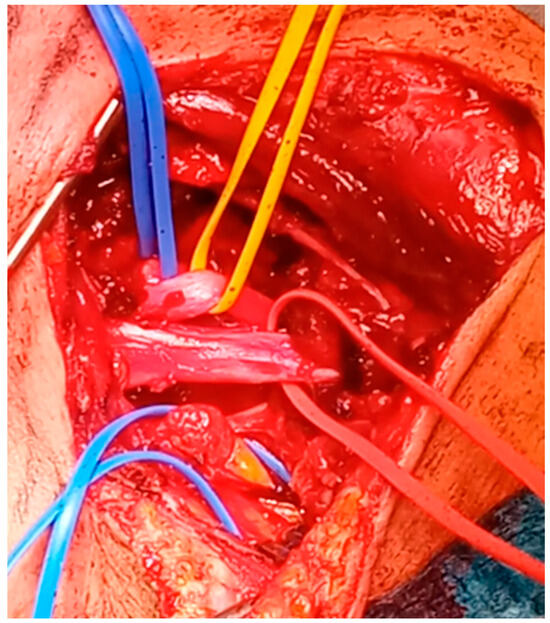

6.2. Surgical Approaches

6.2.1. Transaxillary Approach

6.2.2. Infraclavicular Approach

6.2.3. Paraclavicular Approach

6.2.4. Transmanubrial Approach